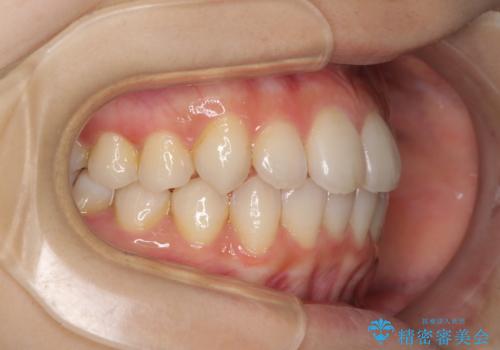

- 前歯のデコボコを気にして来院された患者様です。

叢生と捻転が随所に認められるものの、マウスピースで十分対応可能であったため、インビザラインにて矯正治療を行うこととしました。

マウスピース矯正は毎日しっかりと装着することがとても大切です。

こちらの方はしっかりと指示を守って装着してくださったため、予定通り治療を終えることができました。